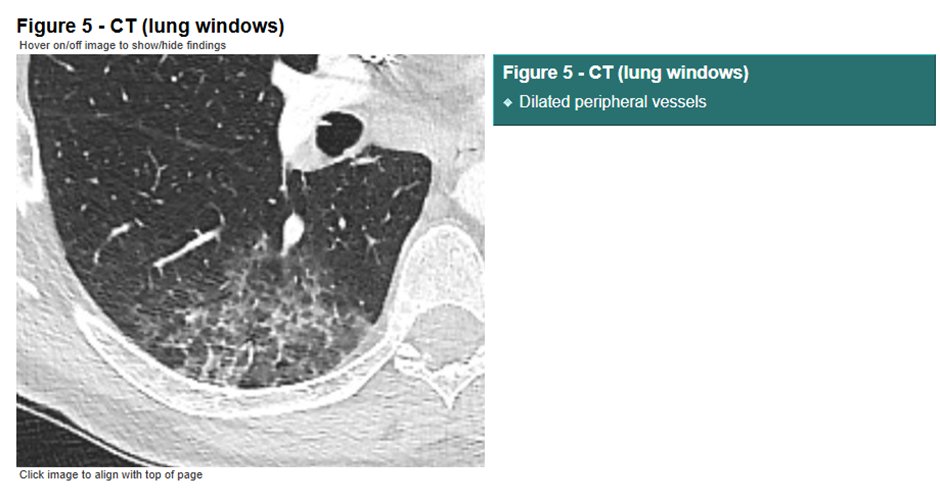

The airways of the lungs were NORMAL!

Unlike influenza, there was no inflammation in the lung airways in people with #COVID-19.

The blood vessels were damaged.

The pattern of lung disease we saw on medical imaging in people with #COVID-19 tells us that the disease is NOT pneumonia, it is a vasculopathy (disease of blood vessels).